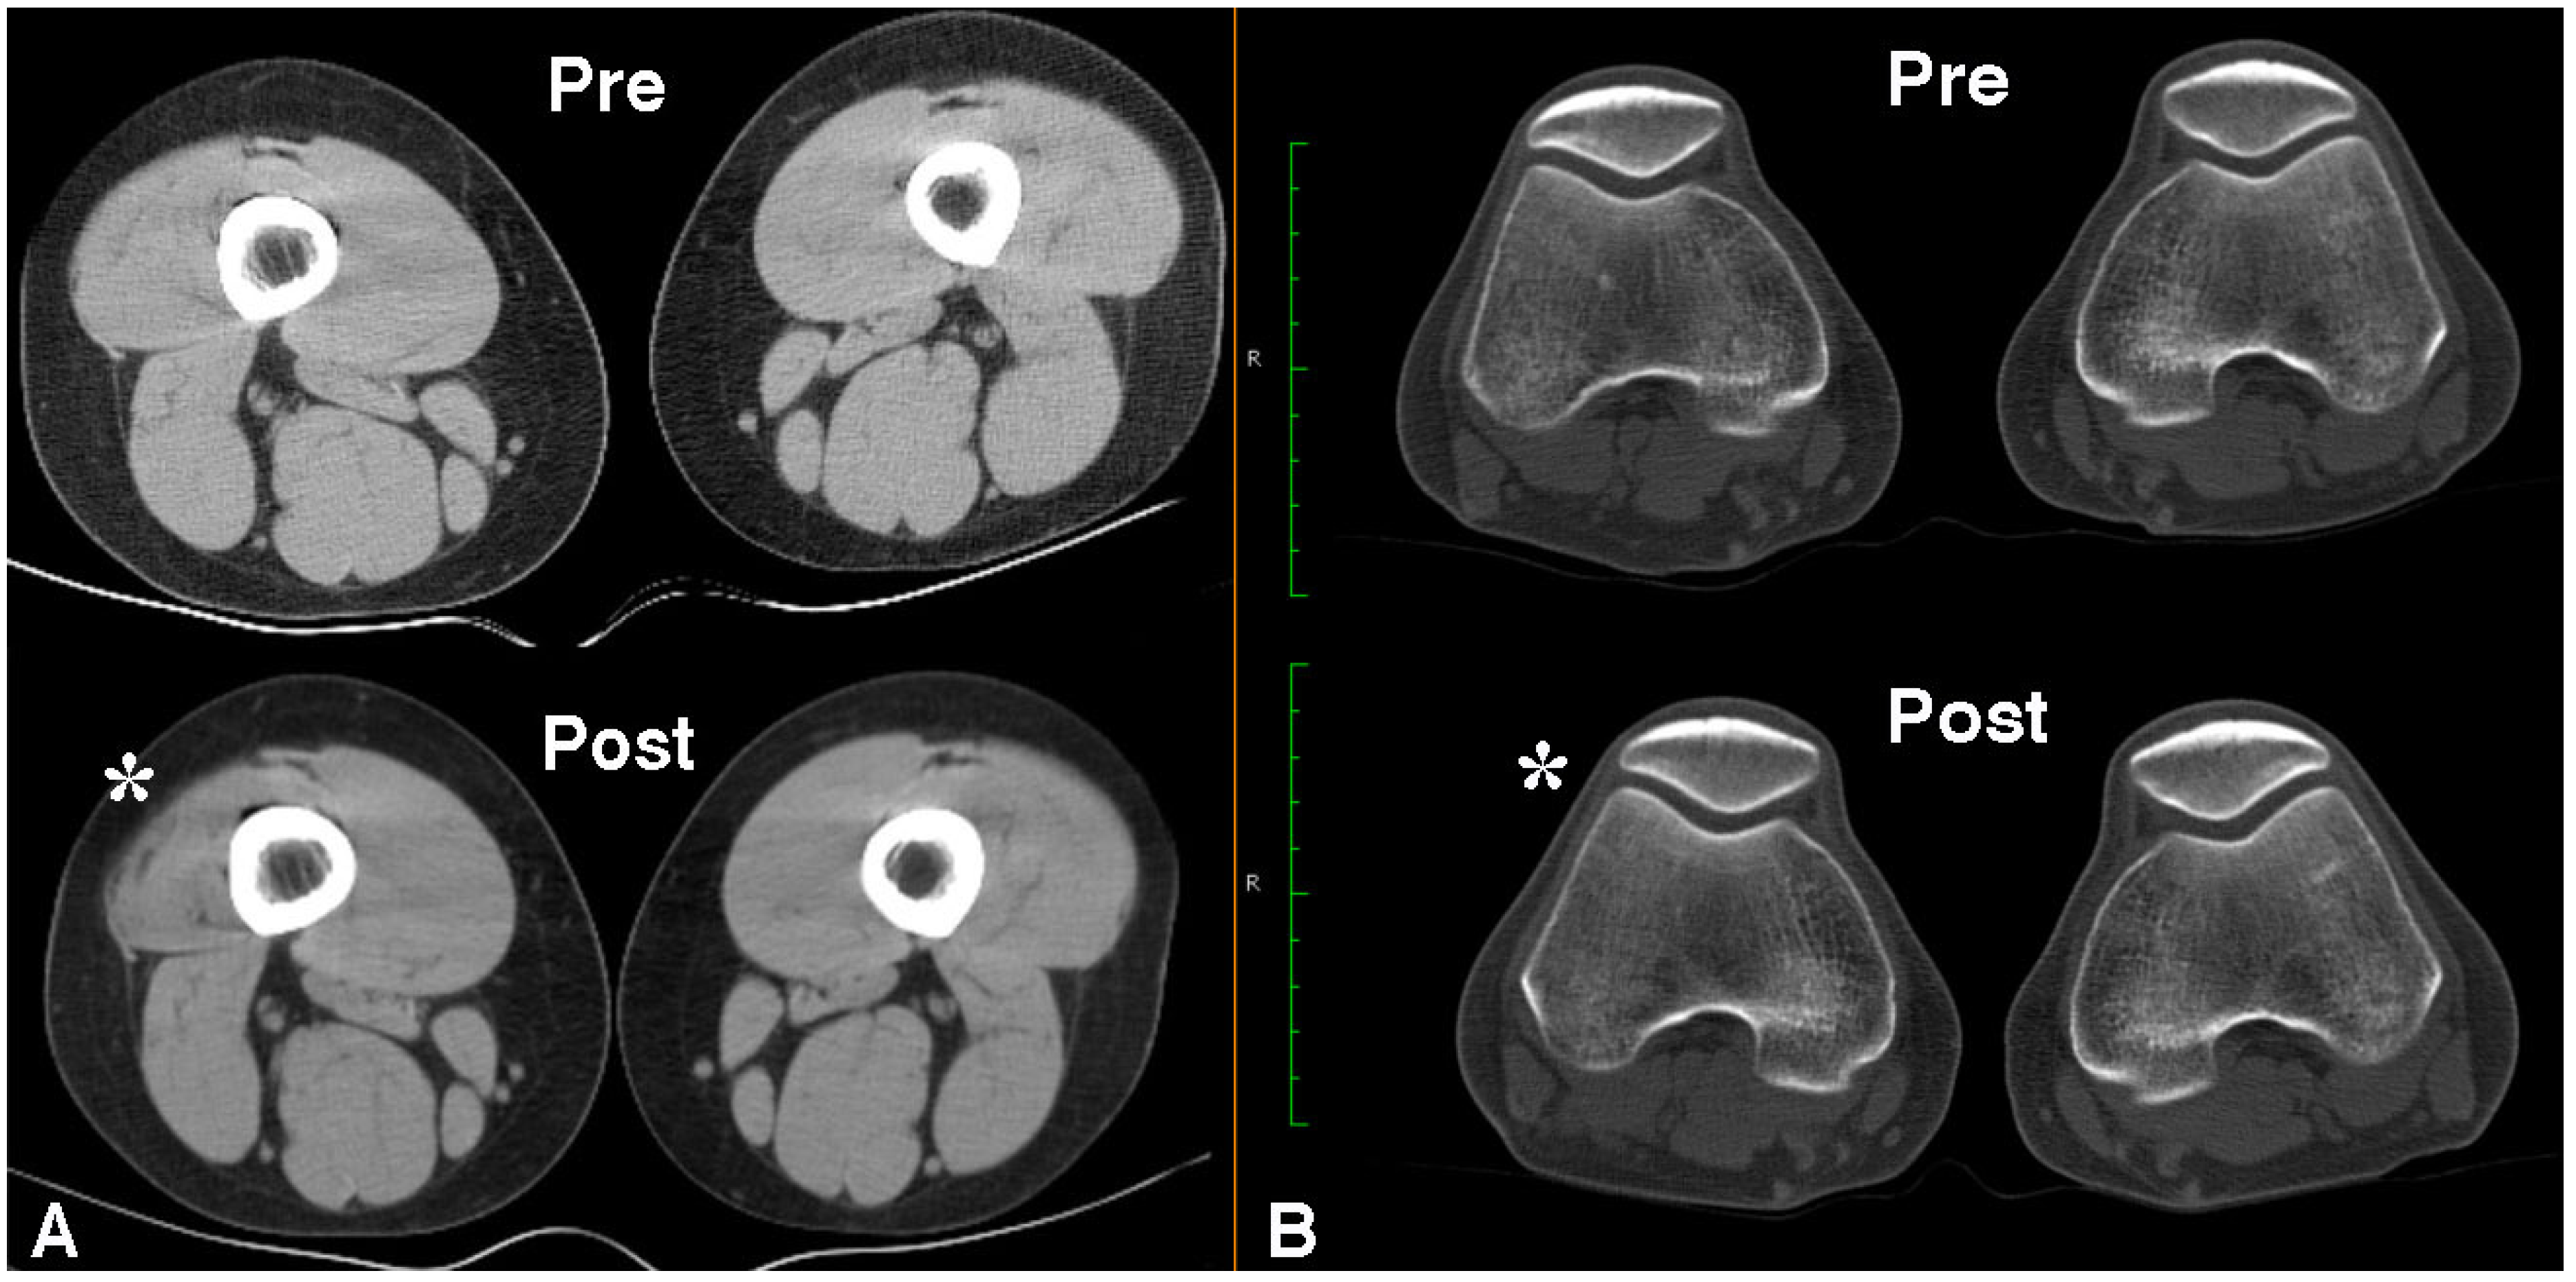

- Singer, B.J.; Silbert, P.L.; Dunne, J.W.; Song, S.; Singer, K.P. Treatment of refractory anterior knee pain using botulinum toxin type A (Dysport) injection to the distal vastus lateralis muscle: A randomised placebo controlled crossover trial. Br. J. Sports Med. 2011, 45, 640–645. [Google Scholar] [CrossRef] [PubMed]